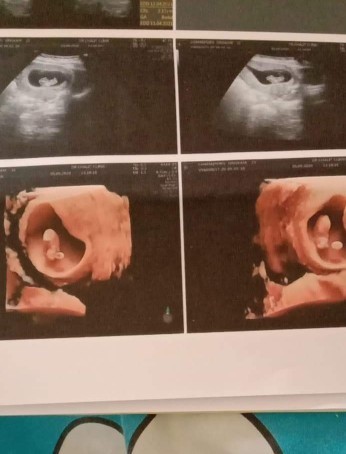

อยากทราบว่าคุณแม่แต่ละท่านซาวด์หน้าท้องเจอตัวเด็กที่อายุครรภ์เท่าไหร่คะ

คือบ้านนี้หมอบอกว่า อายุครรภ์ 4 สัปดาห์ ไปซาวด์หน้าท้องมา ยังไม่เจออะไรเลยค่ะ เลยเป็นกังวล

8w ค่ะ เคยไปตอน6w ไม่เห็นตัวน้องเห็นแต่ถุง

บ้านนี้9วีค เห็นตัวและหัวใจเต้นเลยค่ะ

ช้าสุด 9-10วีค ต้องเจอตัวน้องแล้วค่ะ

เจอตอน6w+5dพร้อมเสียงหัวใจน้องค่ะ

6วีค4วันคะ เจอน้องพร้อมหัวใจ